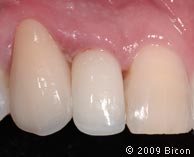

66. Вид интегрированной коронки (IAC).

67. Вид интегрированной коронки (IAC).

68. Вид спереди.